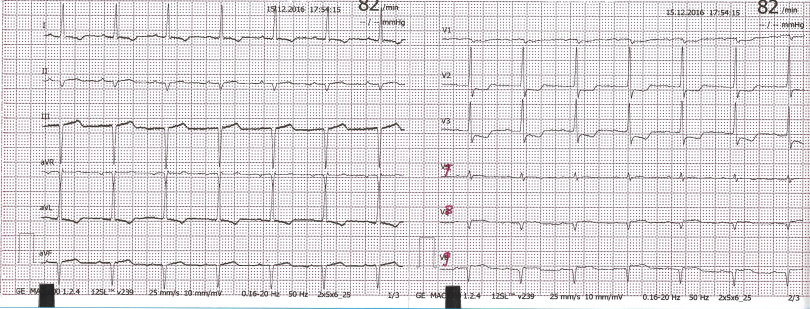

Para confirmar então que a padronização está normal, devemos procurar o retângulo que fica nas laterais do papel do ECG. Este retângulo deve ter 10 quadradinhos de altura e 5 quadradinhos de duração. Exemplo:

Segue um outro exemplo de um ECG com a configuração normal:

Se configurarmos o mesmo ECG para 2N (20mm/mV), a amplitude dos QRS ficará maior e poderíamos dar o diagnóstico de sobrecarga de ventrículo esquerdo de forma incorreta. Por isso é importante checar a padronização do ecg antes de interpretá-lo.

Segue o ECG do mesmo paciente, no mesmo momento, com a configuração 2N:

Da mesma forma, se configurarmos para 50mm/s, poderíamos realizar o diagnóstico de bradicardia ou distúrbio de condução intra-ventricular quando não há nenhuma alteração, como no exemplo abaixo (do mesmo paciente anterior):